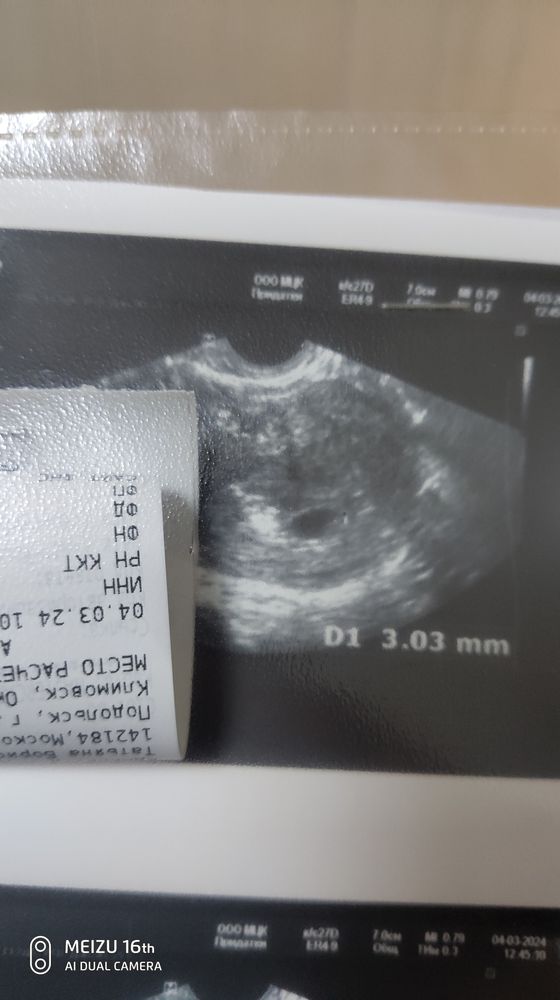

Затрудняюсь с категориейДобрый день. Была неделю назад на УЗИ. 5.2 по М. ПЯ 7 мм ни эмбриона, ни ЖМ. Через неделю,то есть сегодня переделываю узи. ПЯ так так же 7 мм. Ни эмбриона, ни ЖМ. Пошла тут же в другое место. ПЯ намерили 12 мм. Нашли эмбрион 3 мм. Но плодное яйцо дефармтрованно, ЖМ не визуализируется и ЖТ уменьшилось с 22 до 21мм. Сдала хгч. Сказали ждать. Есть небольшой шанс. Как думаете? Было у кого то подобное? Срок по М сейчас 6.2 . Ставят 4-5 недель.

Если действительно нашли эмбрион 3 мм, то это по сроку тянет на 5+6 (отставание до 7 дней в пределах нормы). Смущает, что не нашли ЖМ (без него эмбриона быть не может). Выждать ещё неделю и на УЗИ все будет ясно

Наталья Свешникова, похоже на правду, ПЯ точно 12,5х9 (СВД 10,8 тянет на срок 6+0). По срокам вроде все нормально. Эмбрион тут очень плохо видно. В любом случае через несколько дней переделать (лучше через неделю, чтобы наверняка)